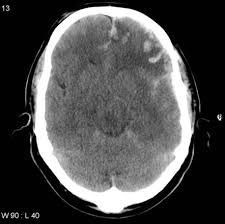

Symptoms Most patients with cerebral contusions have had a serious head injury with a loss of consciousness. Cerebral edema, or swelling, typically develops around contusions within 48 to 72 hours after injury.